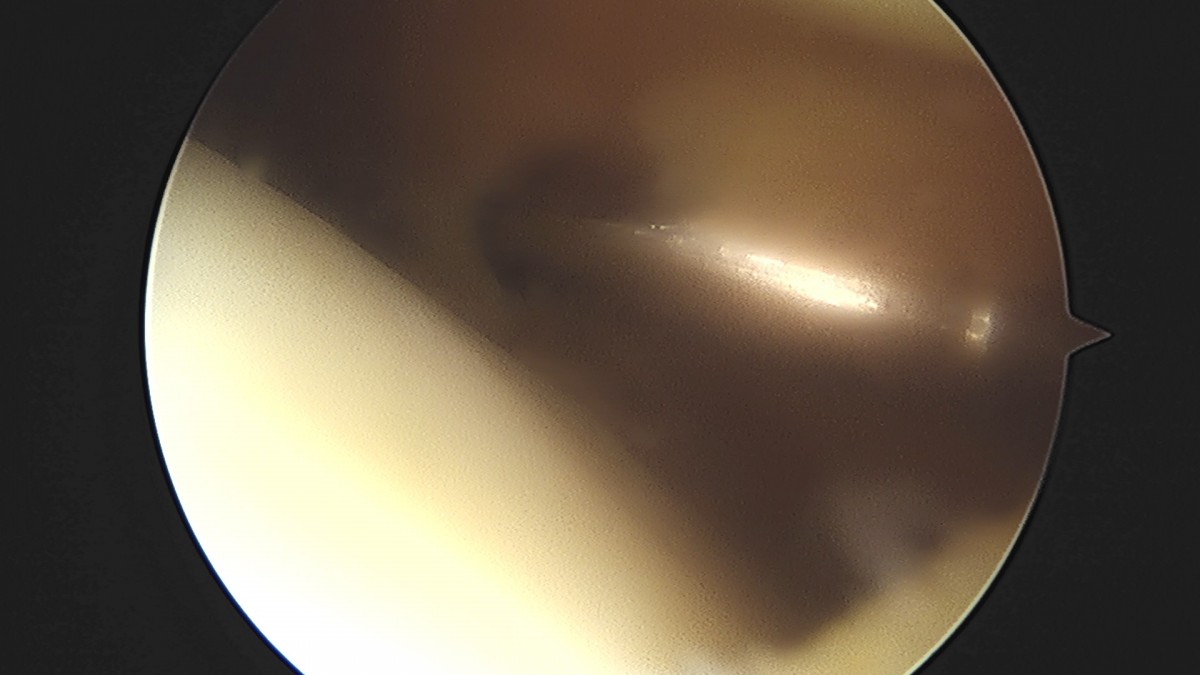

이재상원장님 무릎 전방십자인대 재건술 김태O 환자

작성자 최고관리자 댓글 0건 조회 679회 작성일 25-09-16 16:23